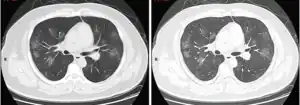

Tomografia computadorizada do tórax

Às vezes, tomografias computadorizadas (TC) do tórax podem ajudar a identificar e caracterizar o estado patológico pulmonar e produzir achados inespecíficos com a infecção por COVID-19. Um estudo descobriu que a sensibilidade da tomografia computadorizada para infecção por COVID-19 era de 98%, em comparação com a sensibilidade da RT-PCR de 71%. No entanto, o teste foi realizado em Wuhan, na China, e, por isso, pode não ser generalizado.[25][26] Grande parte dos achados consistia na presença de opacificação em vidro fosco na região subpleural e pavimentação em mosaico. Esses achados são inespecíficos, pois também são encontrados em outros tipos de pneumonia. Nenhum estudo avaliou, ainda, a precisão e o valor discriminatório das tomografias para distinguir a COVID de outras pneumonias virais.[27][28]

Achados típicos através da TC

Progressão de achado através de TC